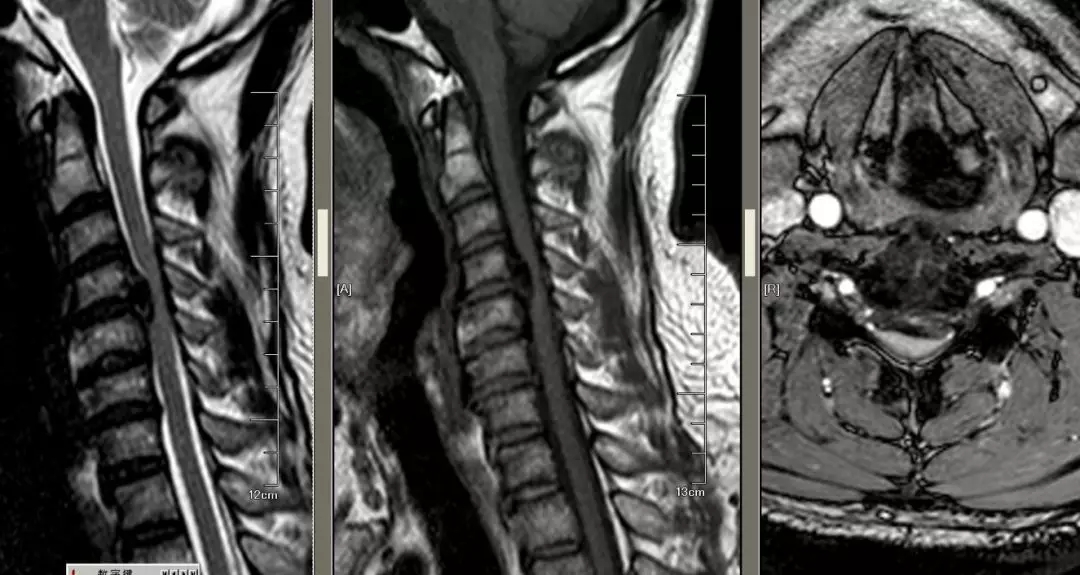

这是由于后纵韧带骨化,也造成了脊髓的受压,和脊髓型颈椎病有很多相似之处,但后纵韧带的骨化在ct相看的更加清楚,后纵韧带的骨化影像分型包括孤立型,间断型,连续型,混合型。它们对脊髓造成的损害,主要是通过挤压,折顶和挫磨引起的。在治疗方面,如果是四个椎节以内的孤立型,间断型可以选择前路手术进行致压物的切除和椎间融合。如果是四个椎节以上的连续型,混合型则选择后路椎管切除,椎管成形术。